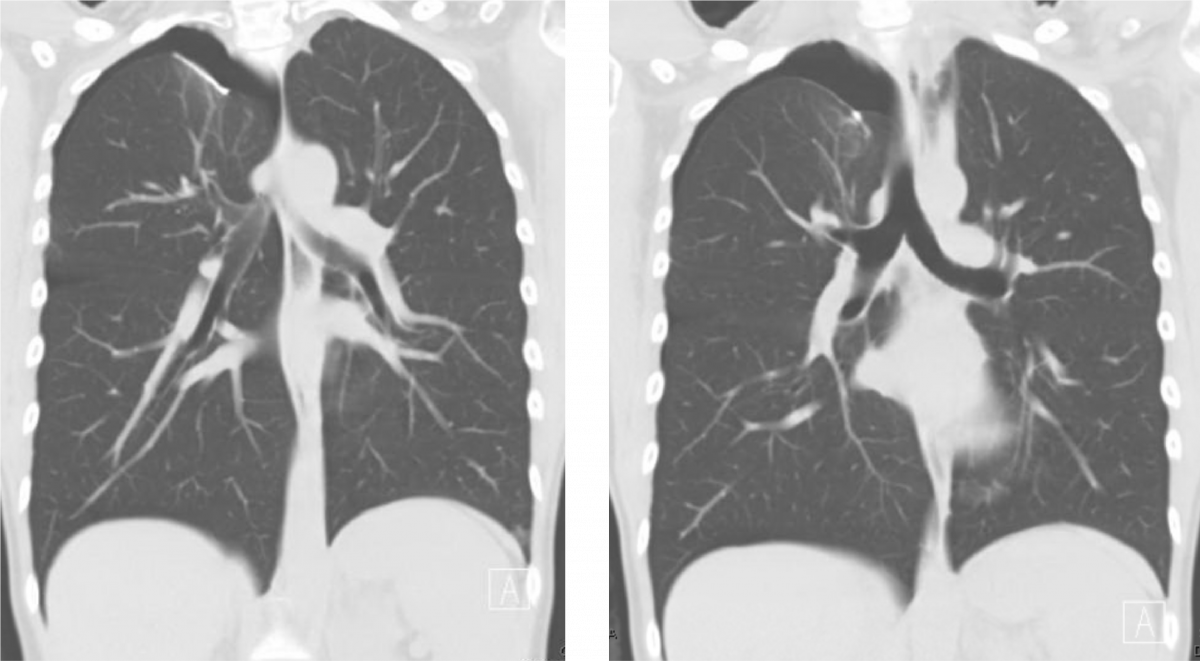

Figure 1. Selected images of the patient’s preoperative computed tomography imaging showing her right apical and basilar pneumothoraxes and pigtail thoracostomy tube.

Figure 1 shows representative images of the patient’s preoperative computed tomography (CT) scan indicating moderate right-sided apical and basilar pneumothoraxes, as well as the pigtail thoracostomy and the prior blebectomy staple line. We offered her a VATS blebectomy, apical pleurectomy, mechanical pleurodesis, and diaphragmatic repair given her persistent air leak with the tube thoracostomy, her frustration with her recurrent symptoms, and her desire to safely become pregnant again in the future.